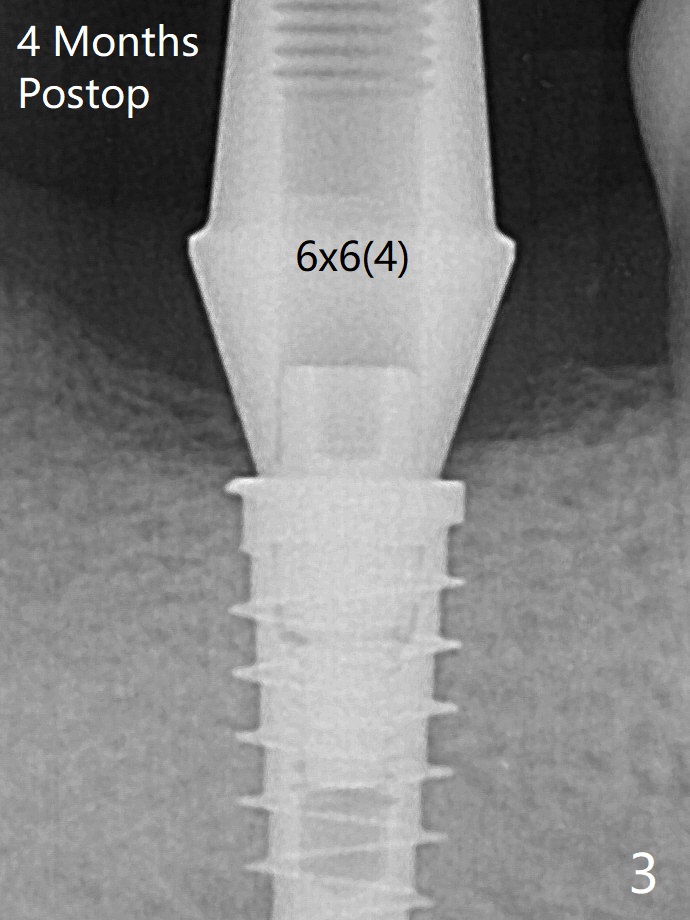

术后四个月更换基台(图三),调整高度后,取模。